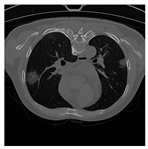

To address contrast-related issues, such as noise and grayscale inhomogeneity commonly observed in CT-scans, the Contrast Limited Adaptive Histogram Equalization (CLAHE) [] method is implemented following the data-scaling step. CLAHE is specifically utilized to alleviate these problems and enhance the visualization of CT-scans. By applying the CLAHE method, image noise is effectively reduced, while simultaneously generating pixels with improved grayscale contrast []. Consequently, CT-scans become more visually discernible, aiding in the accurate analysis and interpretation of the images. A comparative illustration of CT-scan samples before and after the application of the CLAHE method is presented in Table 4 [], highlighting the significant enhancement achieved through this preprocessing technique.

Table 4.

CT-scan comparison before and after CLAHE application [].